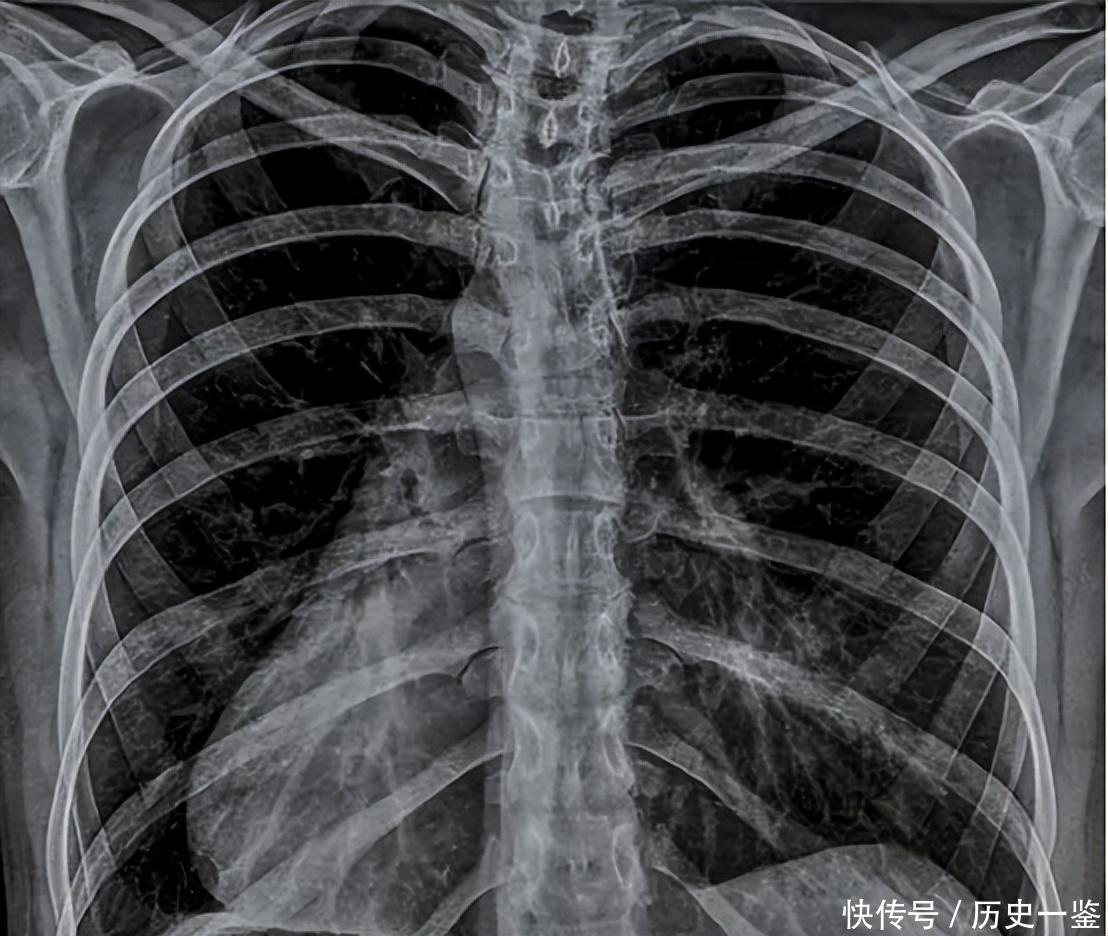

继而将导管顺着血管路径送入冠状动脉开口,最后利用造影剂,在X光下即可清晰呈现血管活动的具体情况。

这种检测方式的优势在于,成像更为清晰,观察起来更加方便。

尤其是血管状态,像动脉狭窄、内壁斑块,包括组织结构异常造成的闭塞等问题,都能在X光下一览无遗。